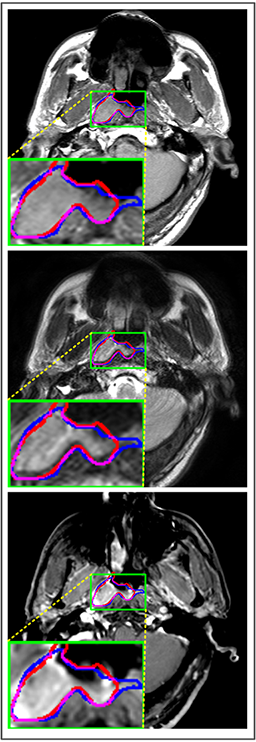

Comparison with ground truth. Some predicted results of MMFNet are shown in 2D images and 3D images in Figure 7 and Figure 8. As shown in these figures, although the shape and size of NPC are varied from each other, MMFNet can still accurately determine the regions of NPC and obtain the accurate contours of tumors. Through analyzing 2D images in figure 7, MMFNet has a capacity to fuse multi-modality MRI to reduce the confusion brought by intensity’ similarity between nearby tissues and NPC. The values of , and of MMFNet are shown in Table 1. MMFNet can reach the best results with , and .

Comparison with related works. Table 1 reports the values of , and for different methods. Predicted masks of different methods are illustrated in Figure 9 and Figure 10, which respectively present results in 2D and 3D images. Through comprehensively analyzing these results, the proposed MMFNet actually have the following properties:

(i) It directly fuses 3D MRI images rather than 2D slices. Thus, it can effectively use meaningful information from neighboring slices of MRI to realize NPC segmentation. As shown in Table 2, MMFNet can bring , and improvements in and compared to the best method based on 2D images (Multi-modality patch-based CNN). And Figure 10 shows that 3D-based methods have less isolated regions (false positives) than 2D-based ones.

(ii) It segments NPC by fusing multi-modality MRIs with the multi-encoder network. Thus, it can learn complementary and interdependent features from different modalities of MRI for final decisions. Additionally, comparing with input-level fusion networks and decision-level fusion networks, layer-level fusion networks (including MMFNet) can effectively capture informative features from different modalities of MRI and fuse low-level features and high-level features.

(iii) It uses a fusion block to fuse low-level features from different modalities of MRI and prepare these low-level features for the fusion with high-level features. Thus, it can more effectively fuse information from various sources. It also uses the self-transfer strategy to initialize the netwerk. Hereby, it can stimulate encoders to make full mining of meaningful features from modality-specific MRI. And it finally improve base multi-encoder-based network (Merging encoders’ fetures) by , and in and .